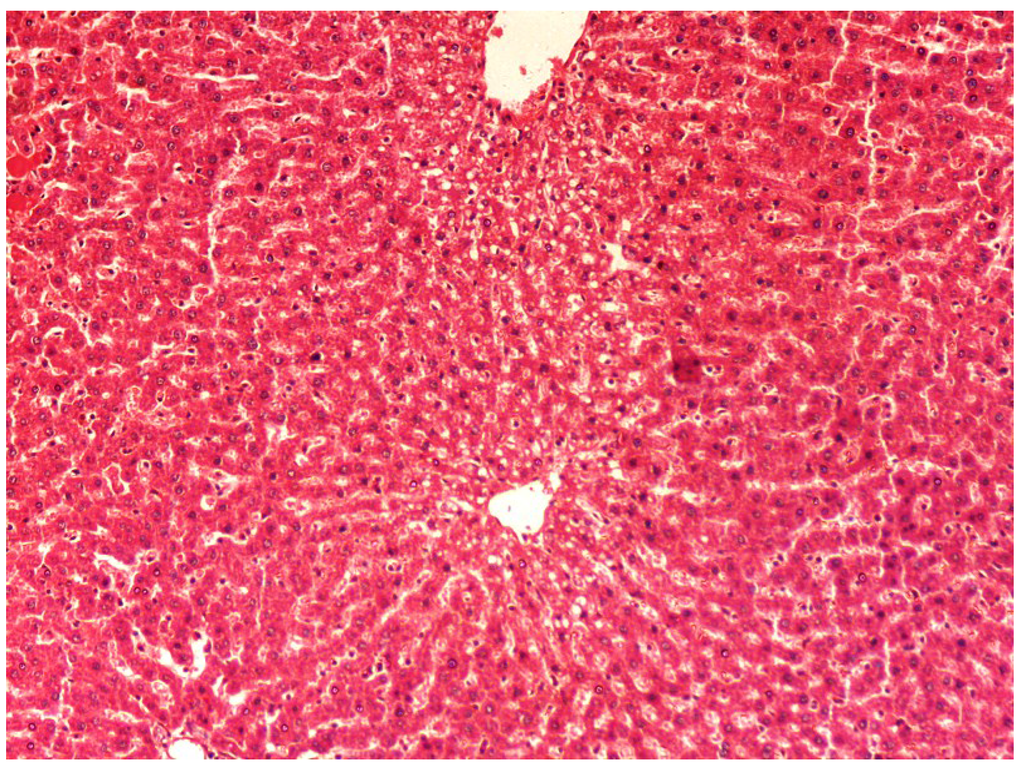

The histopathology of CCl4-induced rats when compared to normal hepatic architecture (Figure 2) showed massive fatty changes, necrosis, ballooning degeneration and the loss of cellular boundaries (Figure 3). The liver sections of plumieride at the dose level of 5 mg/kg body weight plus CCl4-treated rats (Group III) showed mild prevention of CCl4-induced degenerative changes with the few pyknotic nuclei and fatty vacuolizations in the cytoplasm (Figure 4). The liver sections of plumieride treated rats at the dose level of 10 mg/kg body weight along with CCl4 (Group IV) indicated partial amelioration of degenerative effects in hepatocytes but still show cloudy swelling and mild fatty changes (Figure 5). The histomorphological picture of liver sections of plumieride at the dose level of 20 mg/kg body weight along with CCl4-induction to rats (Group V) showed more or less normal labular patterns devoid of degenerative changes, and cytoplasm was preserved with prominent nucleus without intracellular lipid accumulation (Figure 6) almost comparable to the normal control and silymarin treated Group VI (Figure 7).

Figure 5.

Photomicrograph of rat liver section of CCl4 + Plumieride (10 mg/kg body weight), reflecting considerable reduction in necrosis, fatty changes and exhibiting cytoplasmic clearing at H & E × 100.